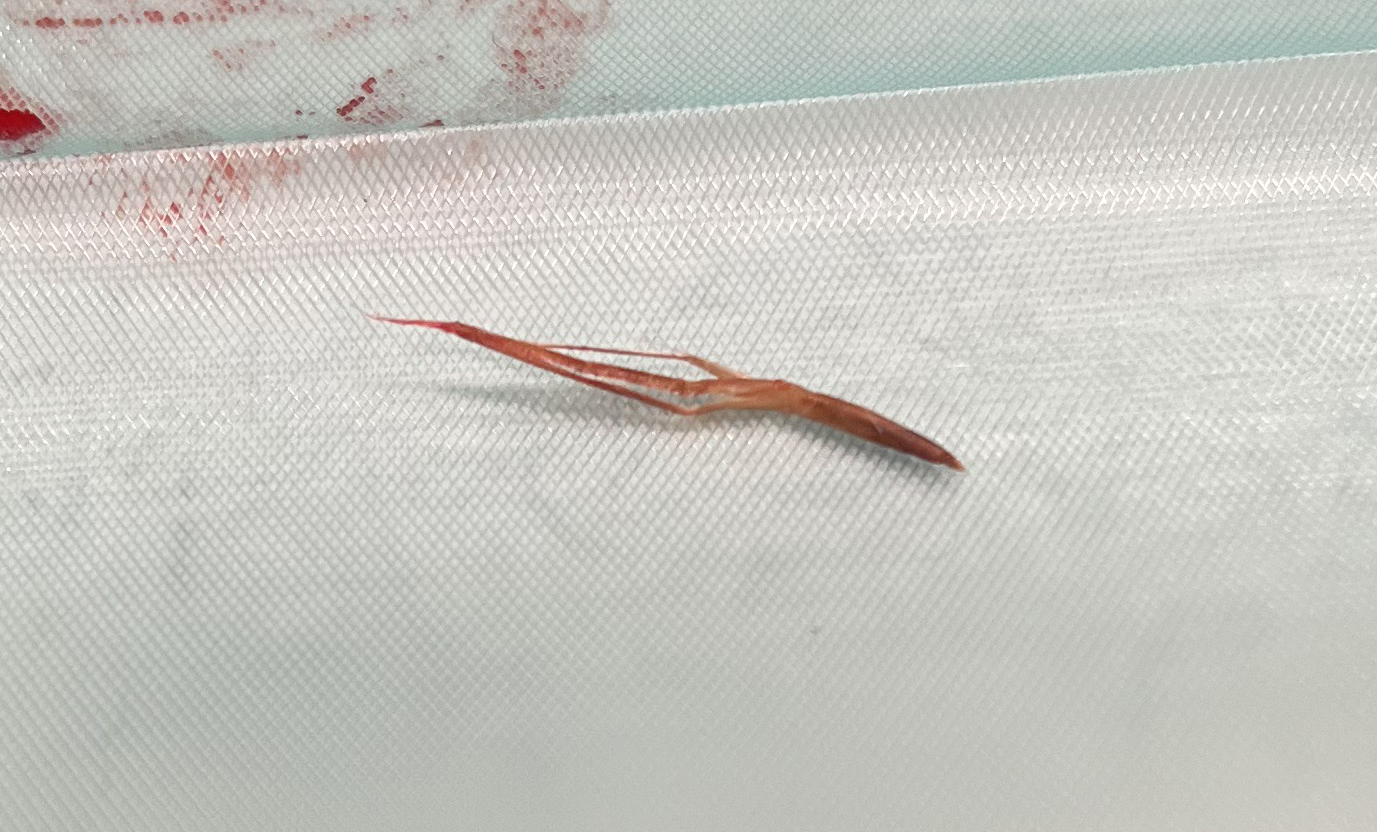

Vervolgens hebben we de strengvormige structuur in zijn geheel verwijderd.

Om zeker te weten dat we alles hadden is het weefsel geopend, voordat we de wond gingen sluiten. In eerste instantie leek het alsof er geen grasaar in het weefsel zat. Maar dit liet maar weer zien hoeveel ons echoapparaat kan vergroten, want op de echobeelden is de diameter van de grasaar 1,5 millimeter en 12,4 millimeter lang. Na een paar sneden vonden we het steekkanaal en de daadwerkelijke grasaar.